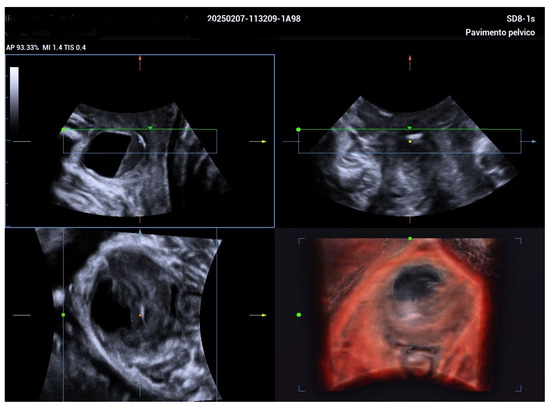

2. Case Report

| Jeong et al. [5] | Suprapubic pain, purulent discharge, leakage | 5.5 cm | TVUS, TPUS, 3D ultrasound at 34 weeks | Antibiotics; aspiration considered | Planned vaginal delivery | Postpartum diverticulectomy |